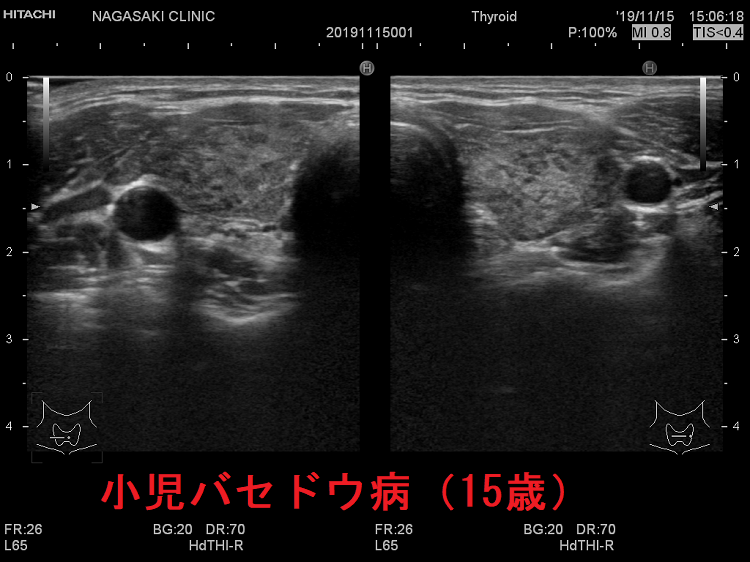

小児バセドウ病(15歳)超音波(エコー)所見は、基本的に成人と同じです。年齢ごとの正常甲状腺サイズの統一基準が無いため、比較は難です。